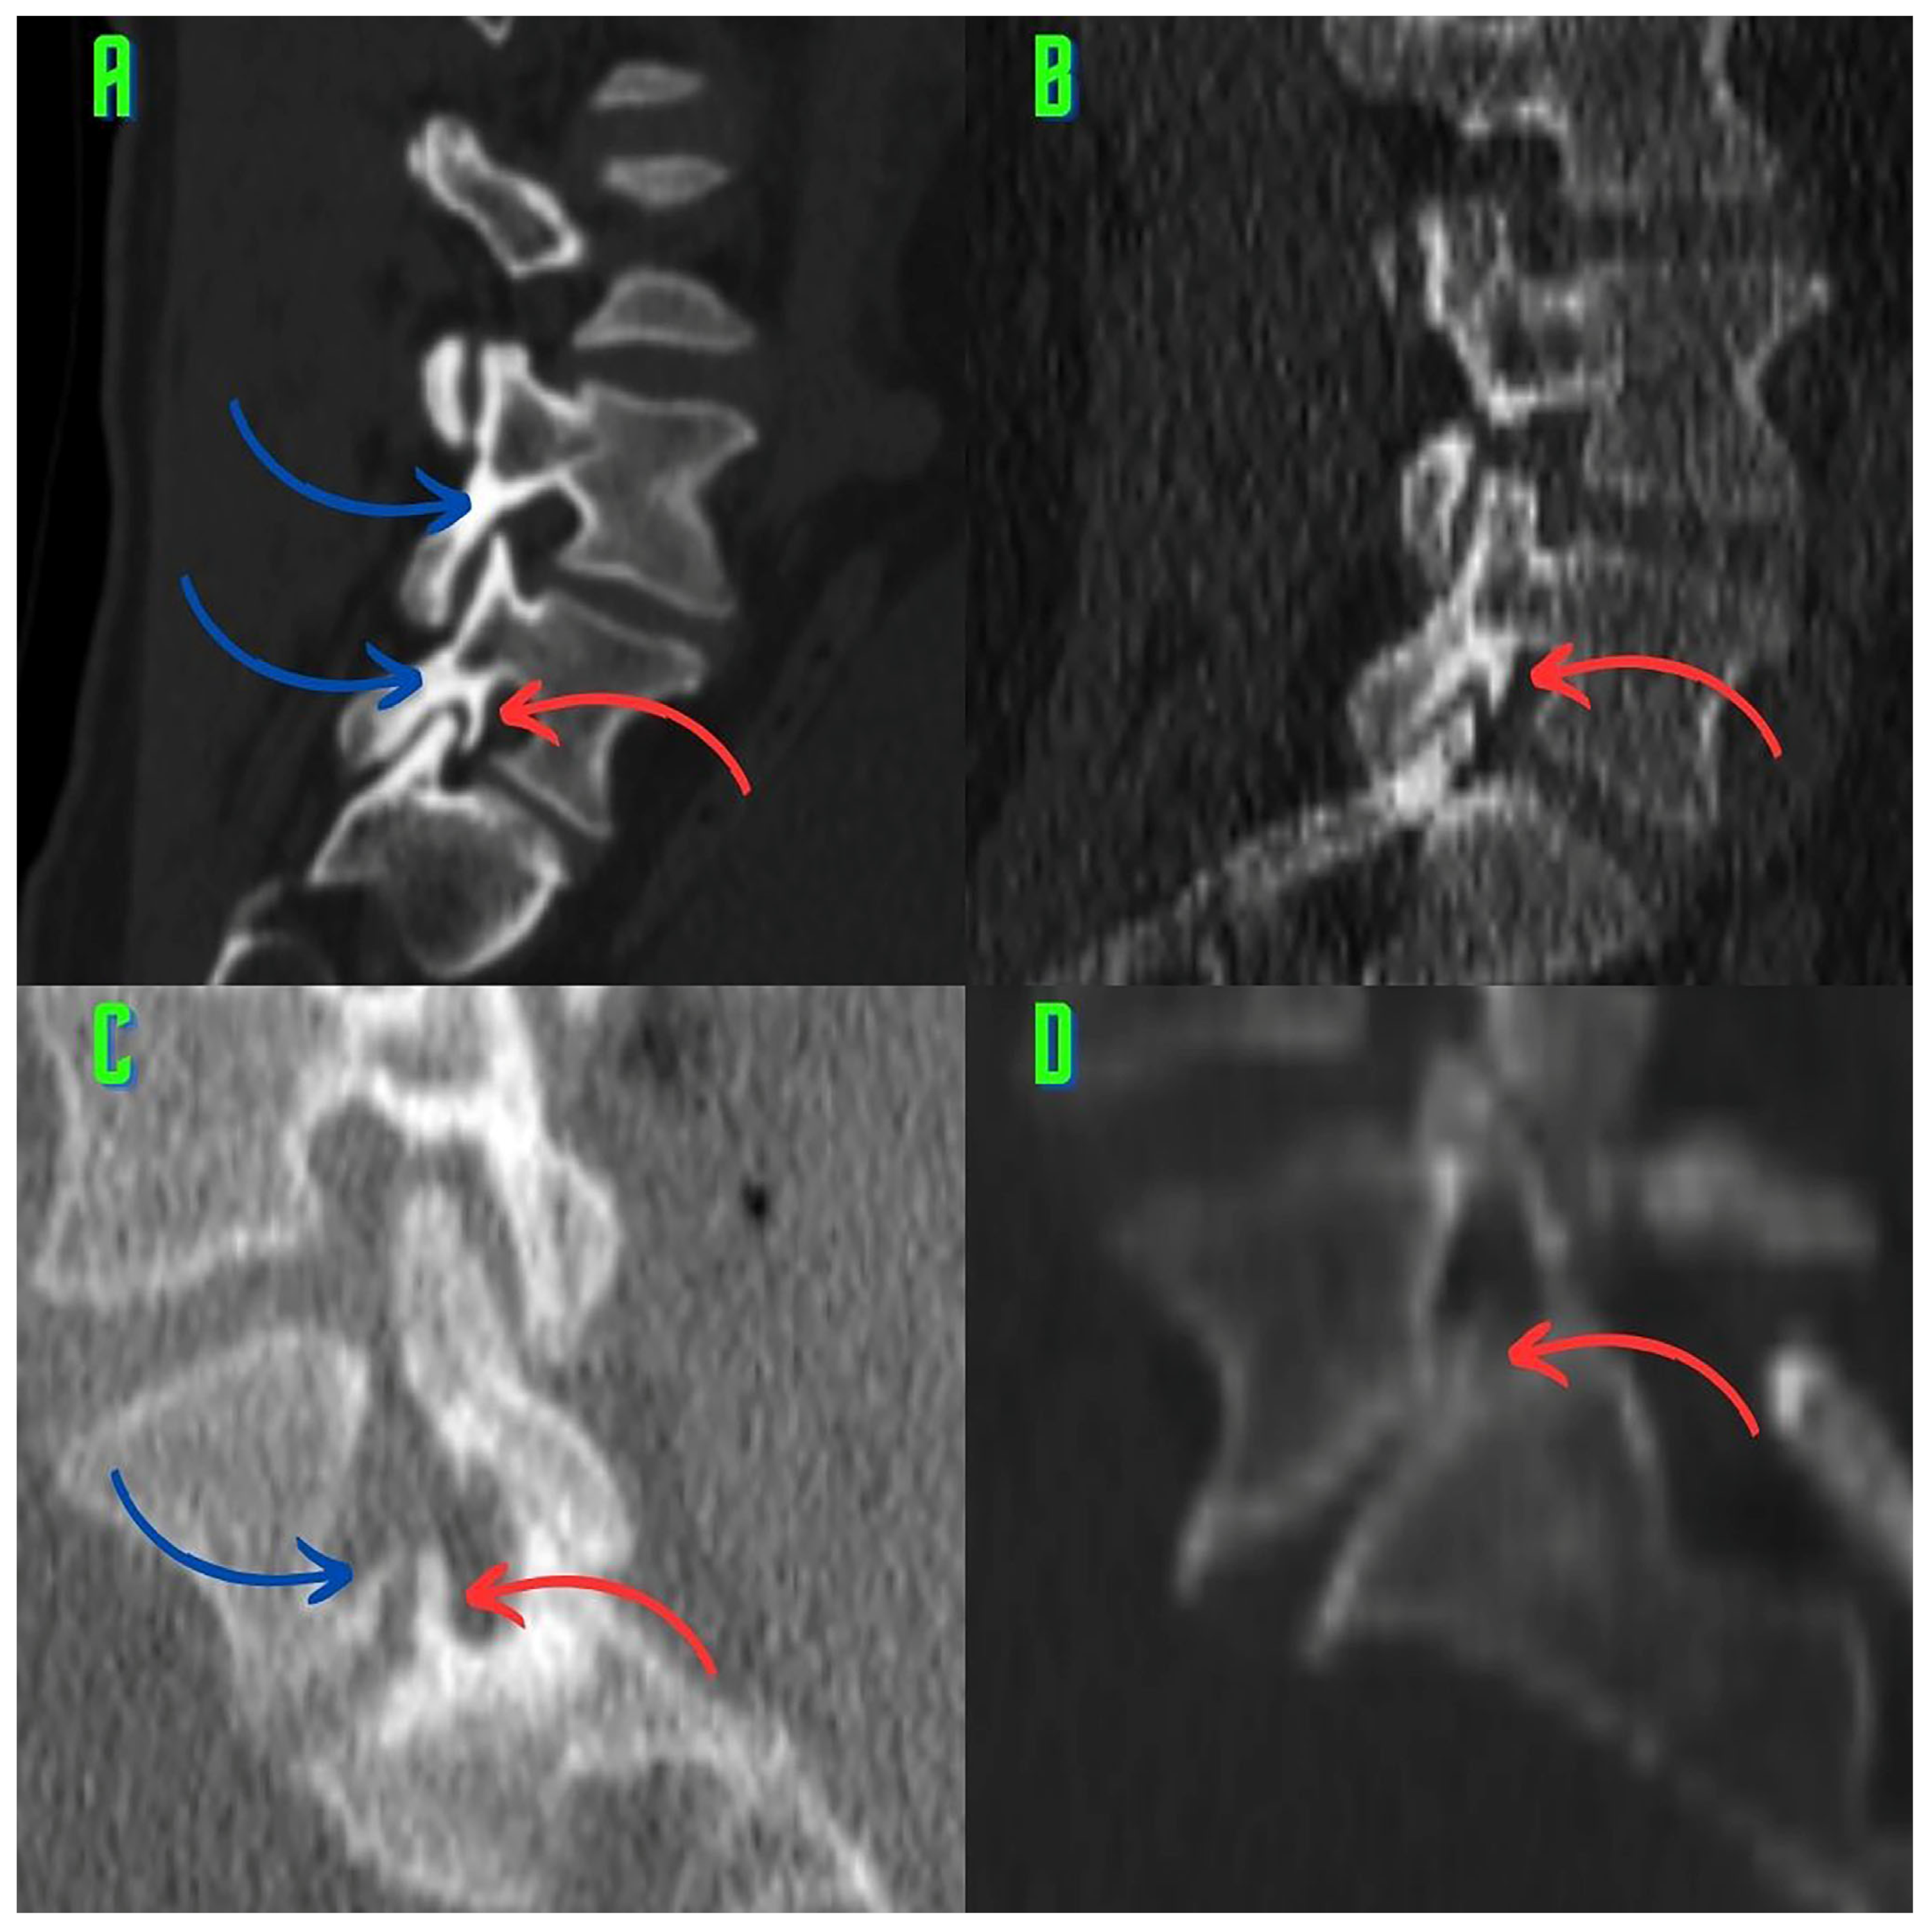

2.3. Image Analysis and Research Methods

3. Results

4. Discussion

4.1. Osteophytes and Facet Osteoarthritis

4.4. Limitations of this Study